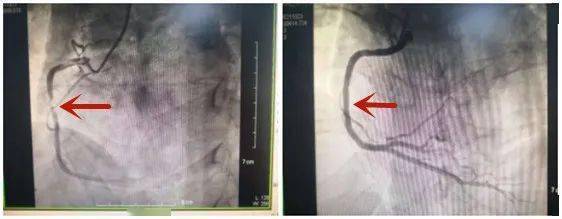

11月8日收治的4位患者中 , 其中一位年龄在70岁左右 。 该患者于8号早晨出门运动 , 在运动过程中突发胸痛、胸闷 , 于是前往医院就诊 。 通过心电图和血管造影检查 , 发现存在严重的心脏缺血和坏死的情况 , 是急性的心肌梗死 。

文章图片

左:治疗前 右:治疗后

图源:苏州市九龙医院心血管内科

随后 , 医院给患者做了进一步治疗 , 目前患者情况已经稳定下来 。